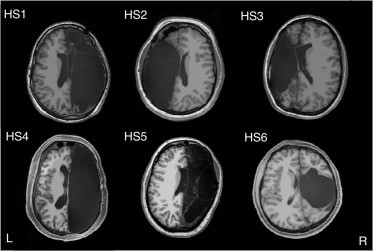

Novejše raziskave delovanja možganov se osredotočajo predvsem na preučevanje funkcijskih povezav v možganih. V raziskavi so s funkcijsko magnetno resonanco v stanju mirovanja posneli možgane šestih oseb z eno samo možgansko poloblo in šestih oseb z obema poloblama možganov. S proučevanjem funkcijske povezanosti možganov v stanju mirovanja lahko namreč preiskujemo tudi druga možganska omrežja, ki so na primer aktivna pri pozornosti, gibanju in kogniciji. Sledili so torej toku krvi po možganih, kar je služilo kot meritev možganske aktivnosti. Pri tem je bila aktivnost lahko hkrati posneta na več mestih, kar je kazalo na sočasno delovanje regij in na deljenje informacij med njimi.